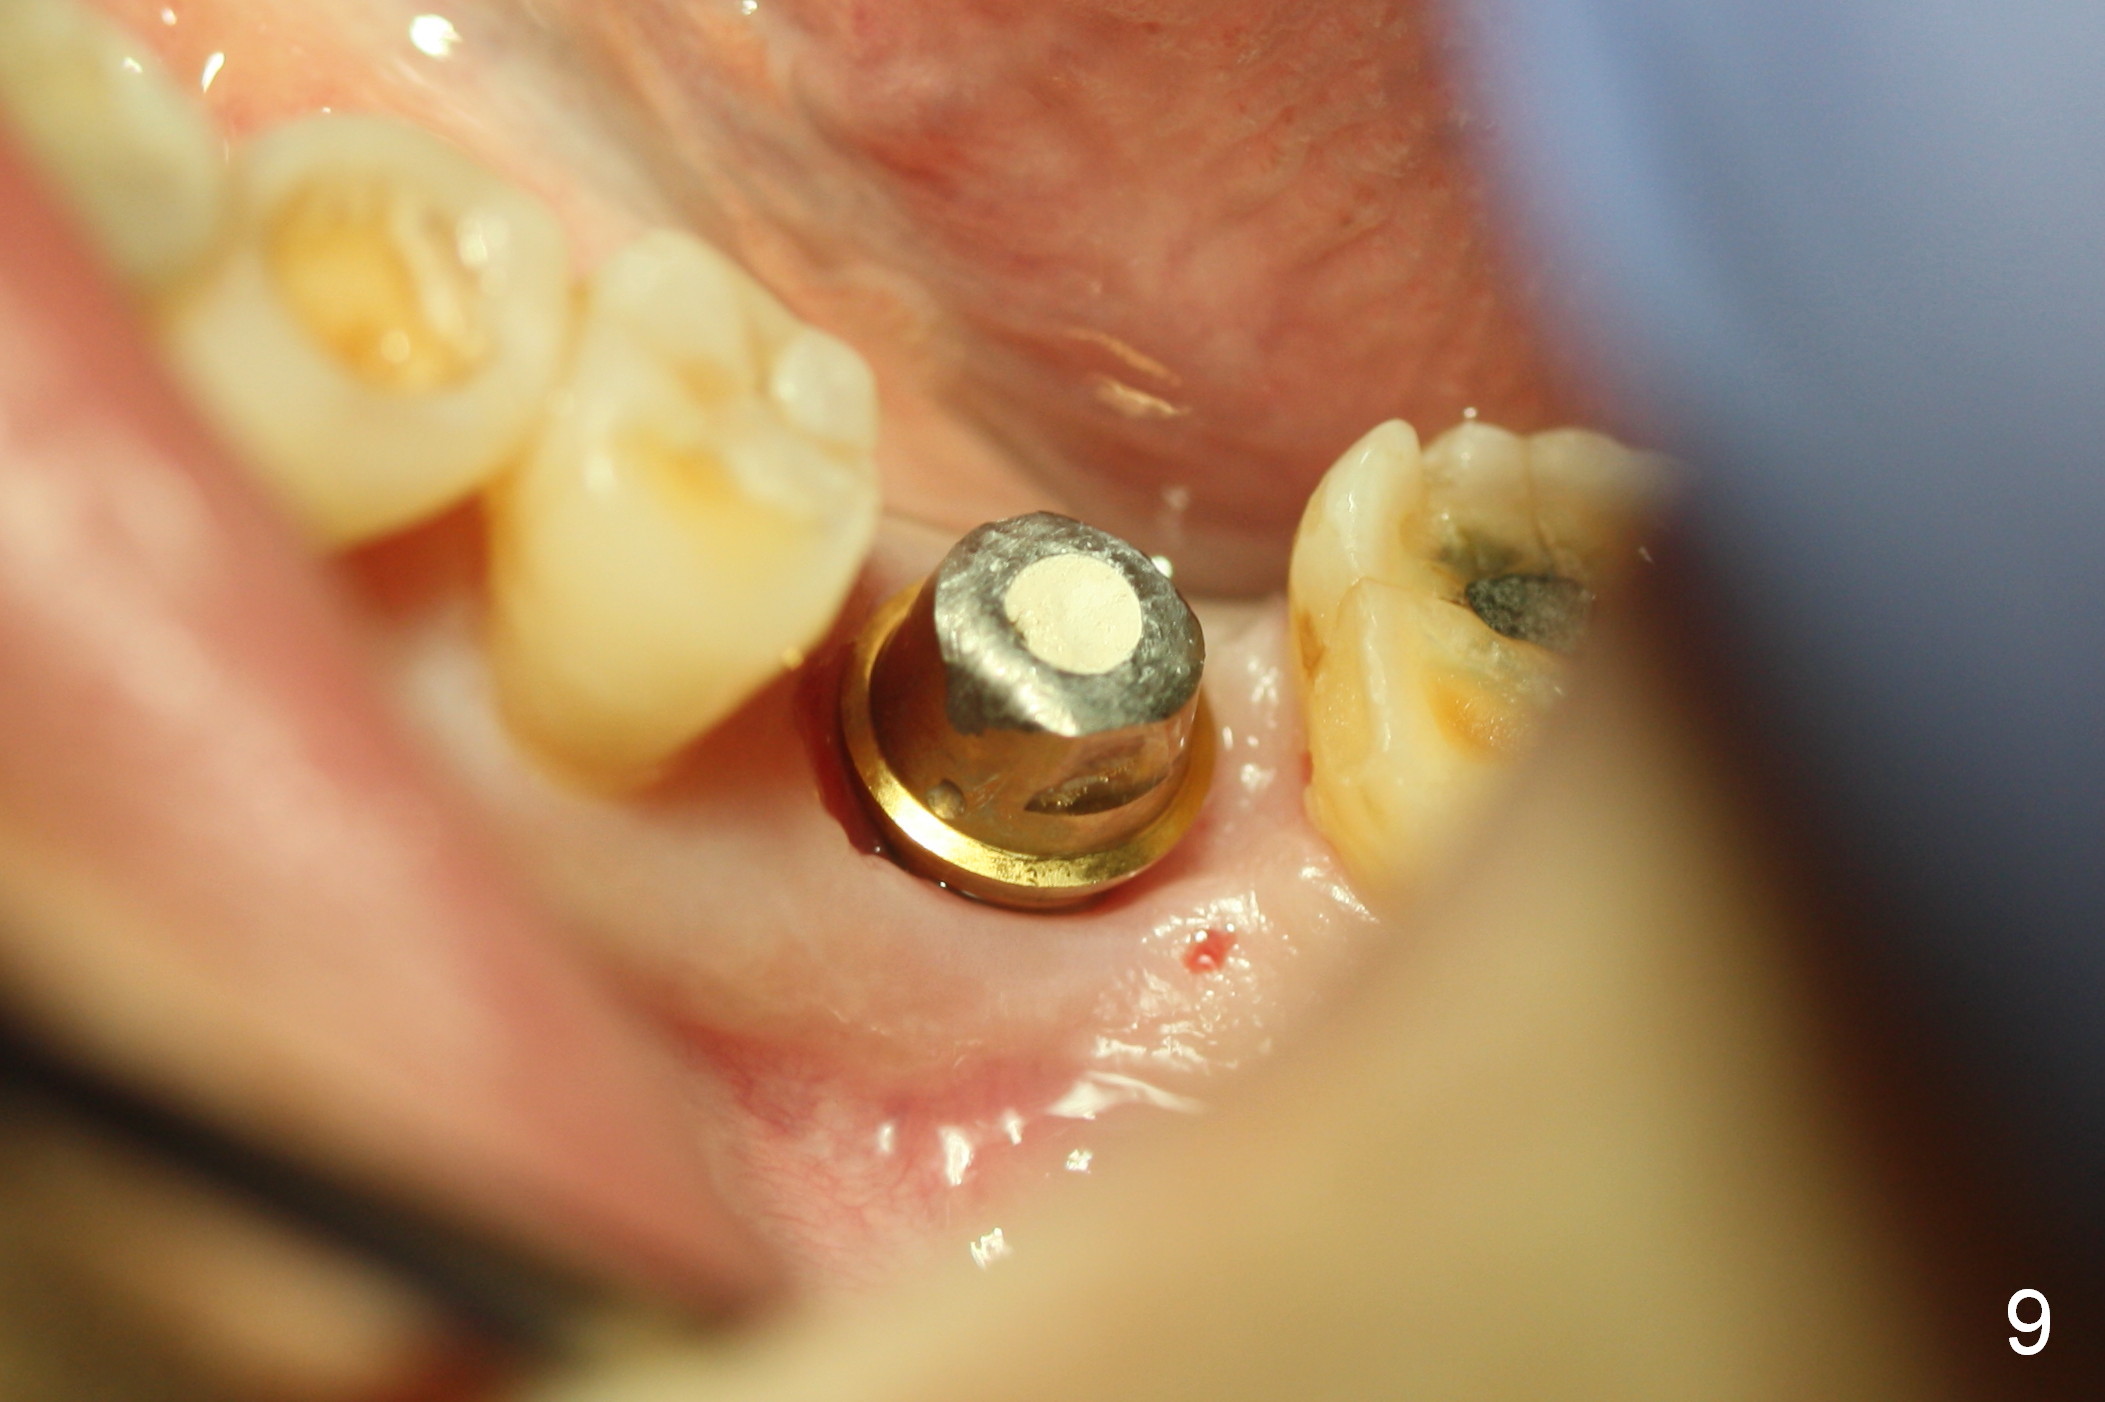

When the patient returns 1.5 months postop, the provisional has been fractured (Fig.8 lingual view). The abutment is loose. Intraop analysis of a PA shows existence of the peri-implant defect (Fig.7). When the abutment is removed, the implant is found to be stable. As a new smaller abutment (Fig.9: 6.8x4(3) mm) is being torqued at 35 Ncm, the abutment/implant does not turn. Impression for final restoration is taken. Postop analysis of PAs in Fig.6,7 shows that the peri-implant defect has been reduced in 1.5 months. Immediately postop, the fourth coronal large thread is buried in the solid bone, whereas 1.5 months postop the third thread appears inside the base bone.

It appears that the loss of the provisional in this case is due to untightening the abutment. The most secure method to fix the abutment/implant in place is to apply setting acrylic to the undercut without taking it out immediately. This is called provisional without cement (1 2 3 4 5). Bone density increases in the peri-implant space 16 months post cementation (Fig.10) and continues to increase 2 years 8 months post cementation (Fig.11).